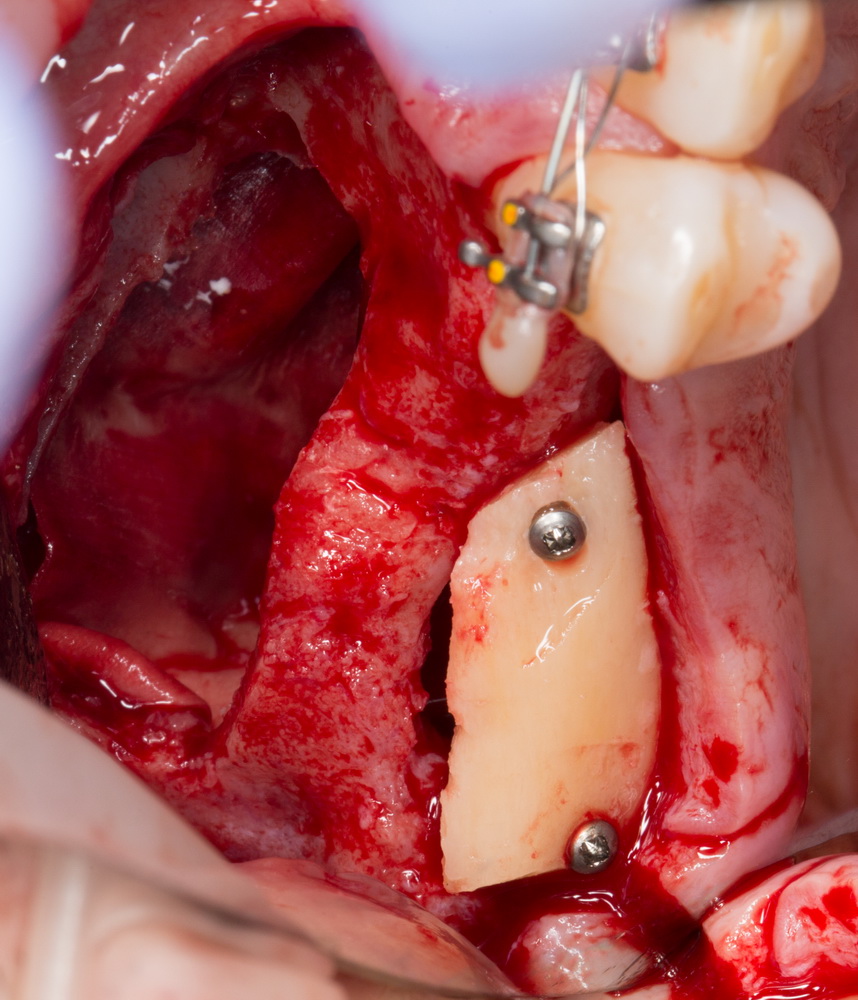

В данном случае я использовал Geistlich Mucograft Seal 8mm. Биоматериал в данном форм-факторе стоит дешевле, чем барьерная мембрана, а его диаметр позволяет легко перекрыть образовавшийся дефект слизистой:

Перед позиционированием Mucograft лучше намочить. Он станет более эластичным (без потери прочности) и мягким:

После чего, он легко приклеивается и перекрывает дефект:

Нам лишь остается заполнить образовавшееся субантральное пространство графтом (Bio-Oss) и закончить операцию синуслифтинга и остеопластики так, как мы планировали: